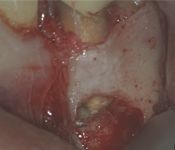

Pictured: Preoperative, Retreatment, Apicoectomy

and 5 Year Recall

Our patient required root canal retreatment. After an apicoectomy, the removal of the root tip and the infected tissue, there was complete bone healing in the 5 year recall.